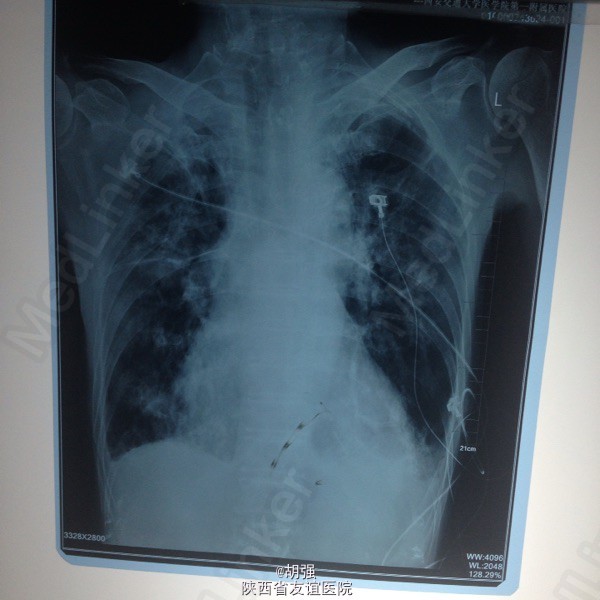

老年男性患者七十六岁。 主诉:反复咳嗽、咳痰10年,加重2月。 现病史:患者10年前受凉后出现咳嗽、咳痰,于当地医院给抗感染治疗后症状消失。此后每遇劳累或者季节交替时,反复出现咳嗽、咳痰、胸闷、气短,且逐年加重,多次住院,行胸部CT、肺功能、血气分析等相关检查,诊断为:慢性阻塞性肺疾病急性加重期,给于抗感染、平喘治疗后均能缓解(具体用药及剂量不详)。2月前受凉后,咳嗽、咳痰、气短症状加重,咳大量白色黏痰,于外院抗感染对症治疗效果不佳,遂来我院。 既往有甲状腺功能亢进病史8年,继发心房纤颤,行I131治疗;有腔隙性脑梗死病史5年。

查体:口唇略紫绀,口腔黏膜无充血、糜烂、溃疡;颈静脉怒张,桶状胸,两侧呼吸动度及语颤减弱,叩诊呈过清音,两肺呼吸音粗糙,可闻及哮鸣音及湿性啰音。心率110次/分,律不齐,心音强弱不等,各瓣膜听诊区未闻及病理性杂音。腹平软,无压痛,肝脾肋下未及,双下肢水肿。 血常规: 白细胞14.01XE9/L、中性细胞比率91%、血红蛋白170g/L、血小板370X10E9/L。

慢性阻塞性肺疾病急性加重期,肺结核?肺真菌病?支气管扩张?慢性肺源性心脏病,心功能IV级,甲状腺功能亢进症,I131治疗后,心房纤颤,脑梗死。 外院给予特治星及氟康唑治疗效果不佳。入院后给予舒普深3.0静注2次/日联合莫西沙星片o.4口服1次/日,多索茶碱0.2十甲泼尼龙20mg2次/日,镁极化液250ml十异舒吉20mg静点,酚妥拉明10mg静点及强心、利尿治疗后好转。